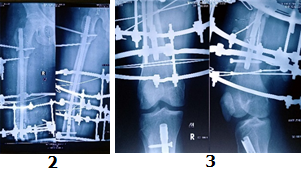

Case-II

26 years, male;

Re-fracture shaft of femur with bending plate and quiescent type infection. H/0-fall (Figure 5-10)

Figure 5 Post-operative x-ray after Plate Osteo-synthesis.

Figure 6 X-ray after re-fracture due to fall.

Figure 7 Post-operative x-ray after mount ilizarov frame kept plate in situ.

Figure 8 X-ray after removal of plate and consolidation.

Figure 9 Post-operative pictures with ilizarov frame.

Figure 10 Pictures after full recovery from fracture after one (1) year and four (4) months.